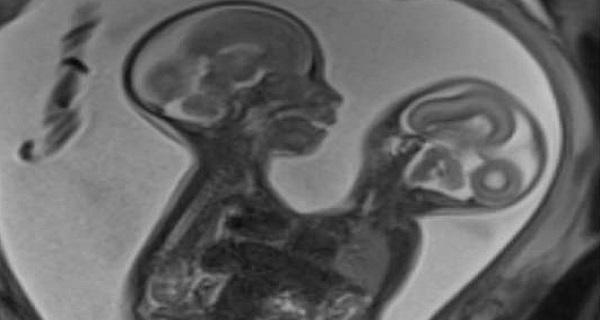

கொழும்பில் ஒட்டிப் பிறந்த இரட்டையர்கள்!